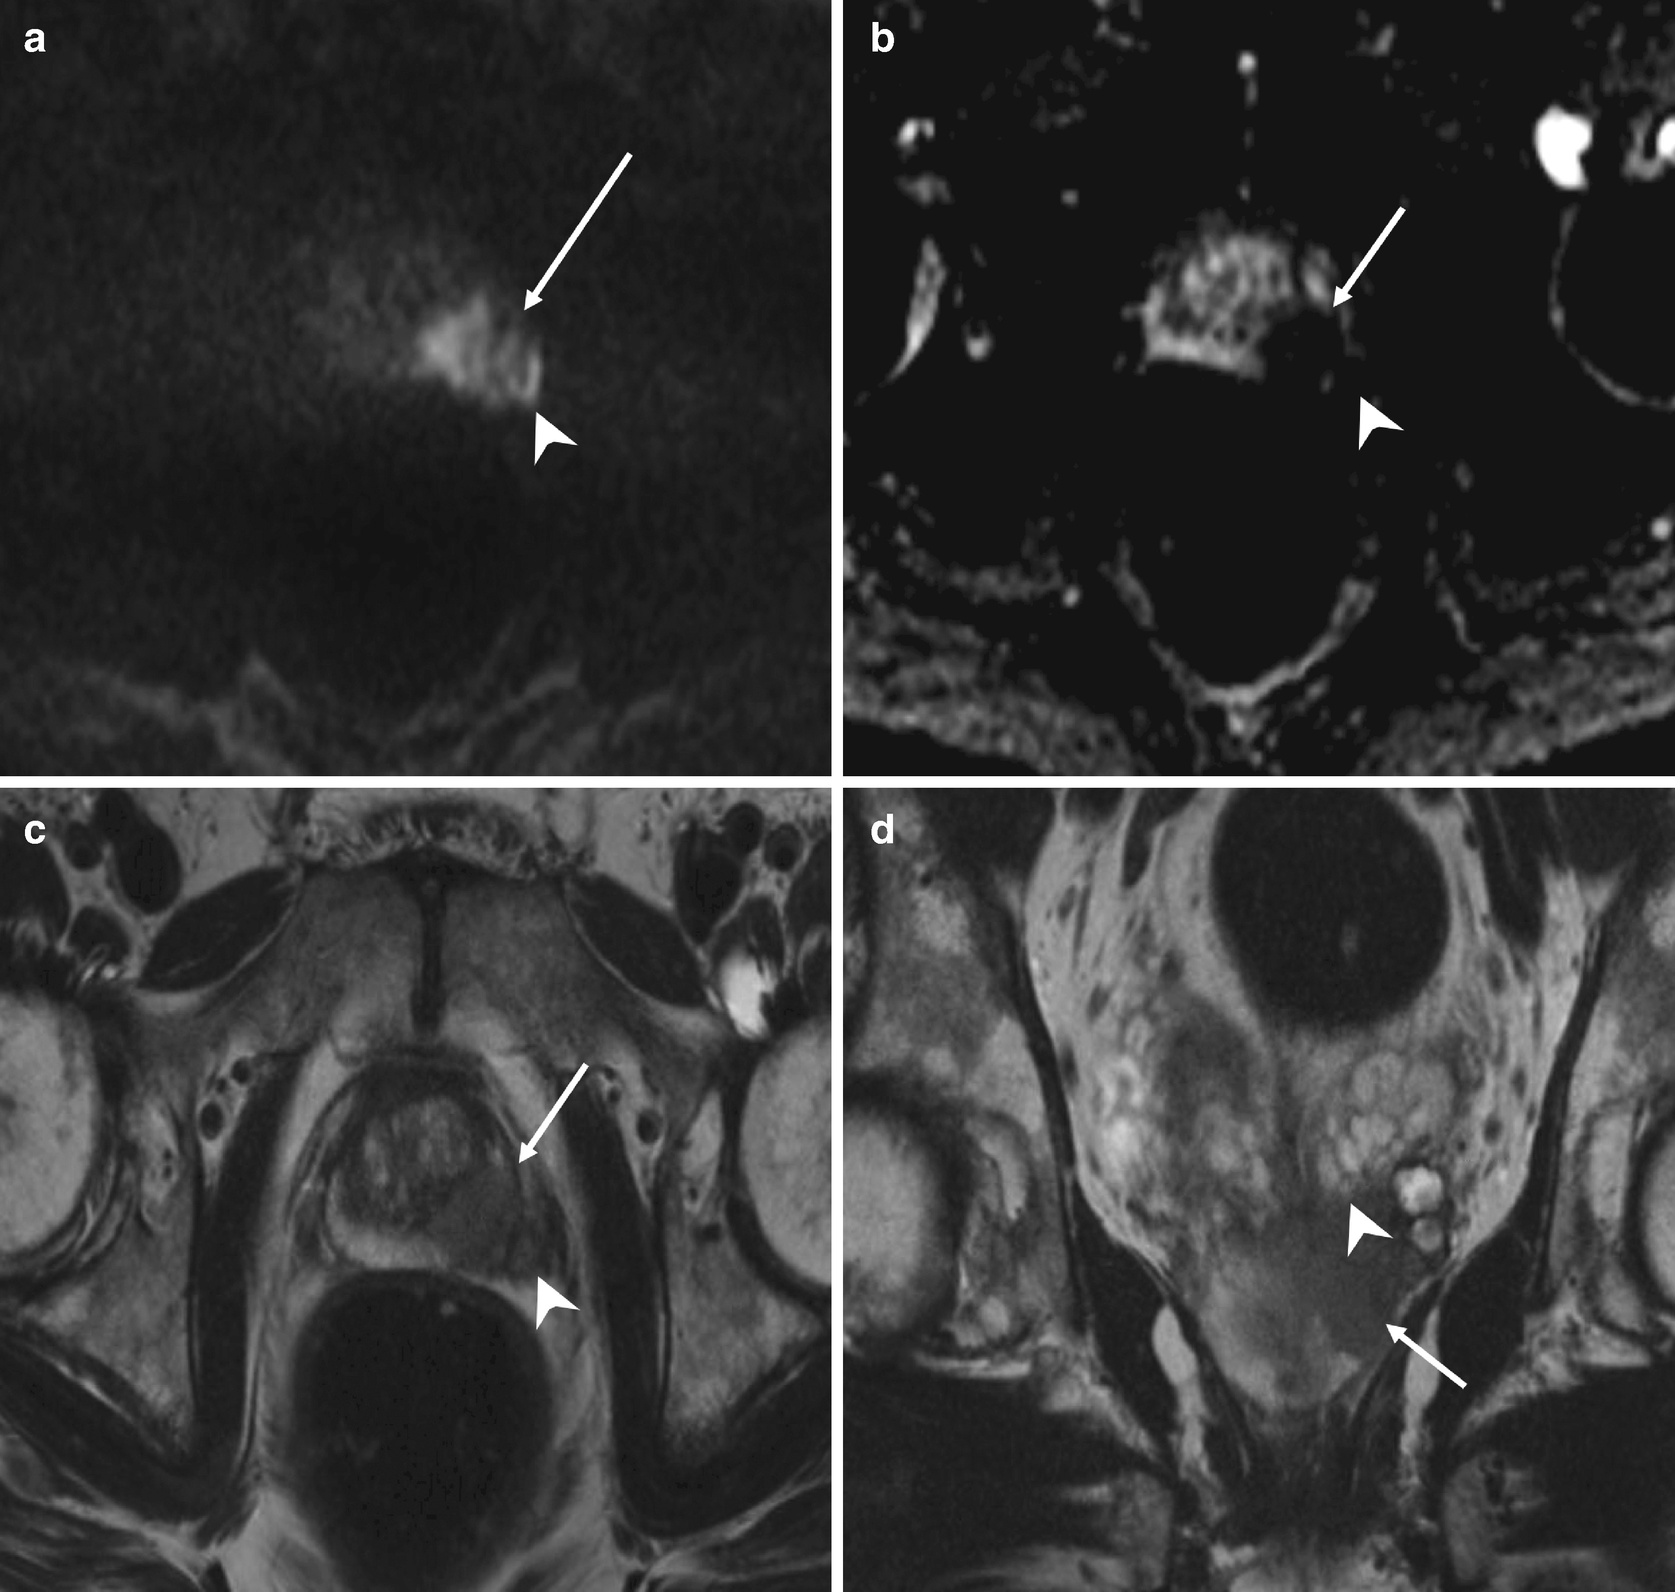

Pi Rads Prostate Imaging Reporting And Data System 2015 Version 2 European Urology

Pi Rads Prostate Imaging Reporting And Data System 2015 Version 2 European Urology from els-jbs-prod-cdn.jbs.elsevierhealth.com